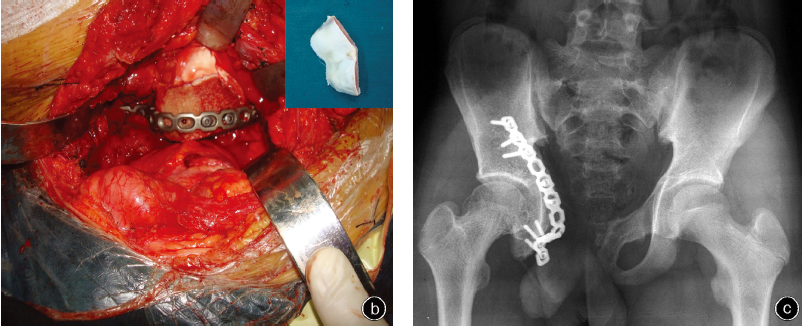

本组8例患者中,3例切除了“Y”型软骨以上的髋臼和相邻的髂骨(TypeⅡA/Ⅰ切除),3例切除了“Y”型软骨前下部分的髋臼和相邻的耻骨(Type Ⅱ B/Ⅲ 切除),2例切除了“Y”型软骨前下部分+后下部分的髋臼和相邻的耻骨+坐骨(Type ⅡB+C/Ⅲ切除 ,表1)。如果肿瘤切除时表面的髂肌未受累,切除边界可认为是广泛切除;如在肿瘤的某一面与血管神经鞘紧邻的部位切除肿瘤,且能较好地分离,则可认为是边缘切除。无论是边缘切除还是广泛切除一旦术中冰冻病理检查发现肿瘤,则需再次行扩大切除直到获得阴性切缘。本组1例患者术中病理检查示切缘仍有肿瘤残存,遂再次行扩大切除。本组5例患者在导航下行精确切除术。

(三)异体髋臼复合重建钢板内固定

术前根据患者骨盆的三维CT数据与数字骨库中的异体骨数据进行比对,选择形态吻合的异体髋臼用于固定。在安全边界内切除肿瘤后,将异体髋臼裁切成相同形状填充缺损,并使用重建钢板固定。本组2例髋臼重建病例,因考虑到需纠正远期肢体生长不平衡,故术中将髋关节旋转中心向远端延长1.5~2.0cm。

本组患者末次随访时MSTS评分为18~27分平均25.4分。7例无骨盆区疼痛(5分),1例为中度疼痛(4分);7例无功能受限(5分),1例中度受限(4分);7例对治疗结果很满意(5分),1例中度满意(4分);7例行走无需支具帮助(5分),1例偶尔需要支具(4分);7例行走距离不受影响(5分),1例轻微受限(4分);7例步态正常(5分),1例步态外观受中等影响(4分)。ISOLS影像学评价为76%~94%,平均90.1%。本组1例患者(病例4)因经济困难而在肿瘤切除术后未行重建。

本组无一例患者术中出现难以控制的出血,术后引流量为700~1500ml。本组2例髋臼重建病例,术中将髋关节旋转中心向远端延长1.5~2.0cm,分别随访4年和6年,髋关节旋转中心达到双侧对称。

本文在其基础上对单一病种(尤文肉瘤)的骨盆肿瘤经“Y”型软骨截骨进行研究,结果显示,所有病变均分布于“Y”型软骨的上、下方,未见肿瘤破 坏“Y”型软骨及病变骑跨。因此,我们认为“Y”型软 骨可能是阻隔肿瘤的天然屏障,对“Y”型软骨未闭合病例,可利用这一天然屏障,借助外科导航技术进行通过“Y”型软骨的精确截骨。肿瘤切除后的缺损通过数字骨库精确配准,选择相匹配的异体髋臼复合锁定钢板进行重建。本组患者通过“Y”型软骨截骨均获得良好的安全边界,术后MSTS功能平均评分为25.4分,至末次随访无一例肿瘤局部复发。